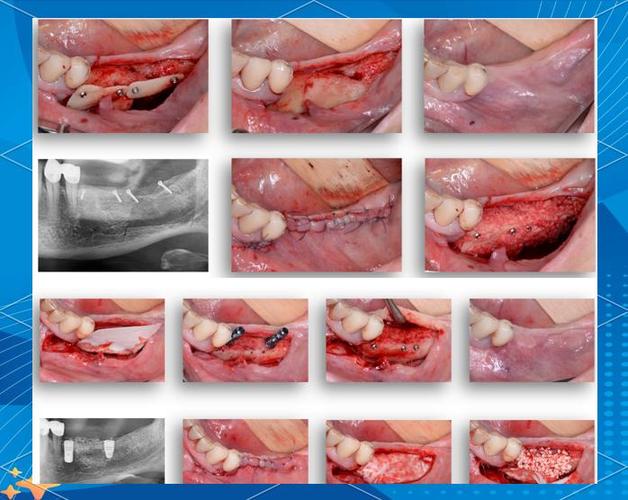

牙齿缺失后,牙槽骨会因失去咀嚼刺激而逐渐萎缩、吸收,就像长期不使用的肌肉会萎缩一样,若骨量不足,种植体(人工牙根)就难以稳定植入,甚至可能穿透骨壁,导致手术失败或远期并发症,骨粉的作用就是补充缺失的骨量,引导骨组织再生,为种植体创造理想的“生长环境”,常用的骨粉包括自体骨(患者自身取骨,如从下颌骨或颏部)、异体骨(捐献者骨骼处理后的材料)和人工骨粉(如羟基磷灰石、磷酸三钙等),其中人工骨粉因来源充足、排异反应低,临床应用更广泛。

骨粉吸收或排出:

- 原因:骨粉与骨组织结合不良(如人工骨粉降解过快)、患者存在吸烟等不良习惯(影响骨愈合),或术中骨粉过度挤压导致周围组织缺血坏死,身体将未结合的骨粉视为“异物”排出。

- 处理:少量吸收无需处理,医生会评估剩余骨量是否足够种植;若大量吸收导致骨量不足,需等待3-6个月待伤口完全愈合后,补充植骨再行种植。

缝合失败或伤口裂开:

(图片来源网络,侵删)- 原因:外力撞击(如磕碰)、咬合创伤、或缝合技术不当,导致伤口裂开,骨粉脱落。

- 处理:小范围裂开可重新缝合并加强护理;大范围裂开可能需取出骨粉,待软组织愈合后再植骨。